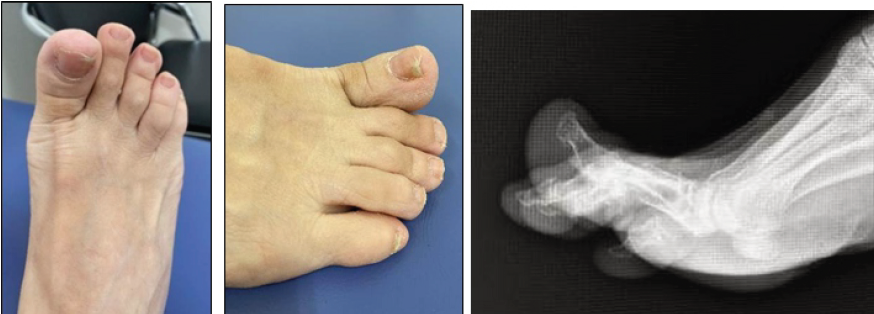

A 71-year-old Asian woman with a history of schizophrenia was admitted to our hospital for specialized care. During treatment, the patient developed severe hyperdorsiflexion and stiffness of the right hallux, causing intense pain, which was particularly noticeable during gait. As the condition persisted, the patient was referred to the orthopedic department for consultation. Physical examination and plain radiography revealed a hyperdorsiflexed contracture of the right hallux at 20° (Fig. 1).

Figure 1: Manifestation of hallux hyperdorsiflexion and stiffness on the dorsal aspect of the right toe, along with corresponding findings on plain radiography.